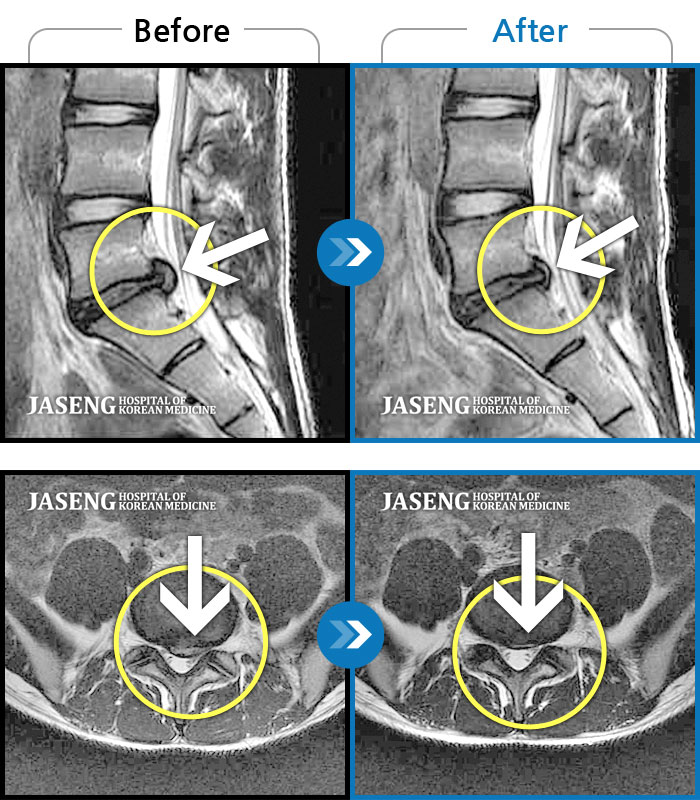

허리디스크

수원 · 김태성 원장

허리 통증과 좌측 대퇴부~종아리 저림과 통증

촬영시기

2011.03.14 ~ 2024.05.24

2024.11.21